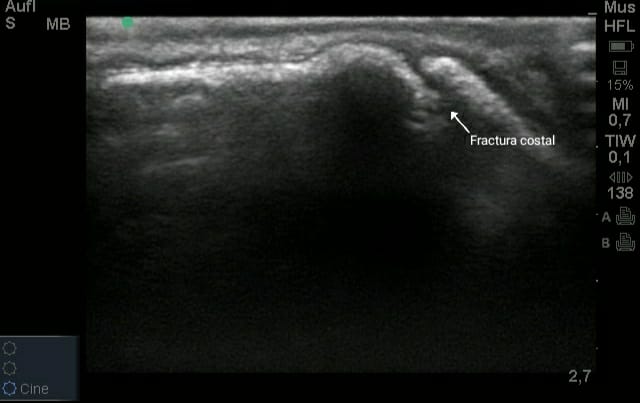

Dado que son síntomas inespecíficos de otras patologías, el diagnóstico definitivo de una fractura de costilla requiere una ecografía, radiografía de tórax o incluso una gammagrafía, donde las fracturas muestran mayor captación de radiofármaco dentro de las 24-72 horas posteriores a la lesión, lo que lo convierte en un método diagnóstico altamente sensible en la etapa aguda de la enfermedad en comparación con la radiografía que puede no observarse alteración hasta pasados 7-10 días del acontecimiento traumático, a menos que sea una fractura desplazada.

La ecografía resulta un método diagnóstico de gran utilidad tanto en la fase aguda de la enfermedad, como posteriormente para el control de la cicatrización, facilitando la identificación de los casos que no evolucionan correctamente y requieren intervención quirúrgica.